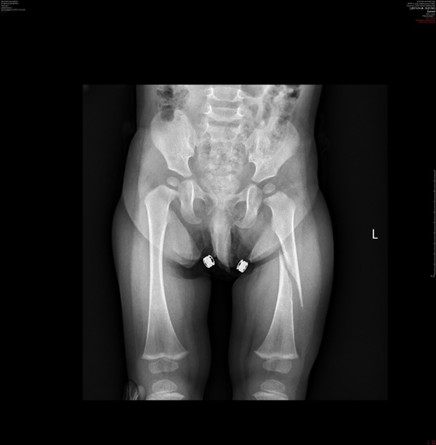

Zdrowy 16-miesięczny chłopiec trafił do izby przyjęć. Rodzice poinformowali lekarza dyżurnego, że dziecko upadło w domu potykając się o niewielką przeszkodę. Lekarz dyżurny zlecił wykonanie zdjęcia radiologicznego kończyn dolnych widocznego poniżej:

Co powinien wykluczyć lekarz, zanim przystąpi do leczenia?